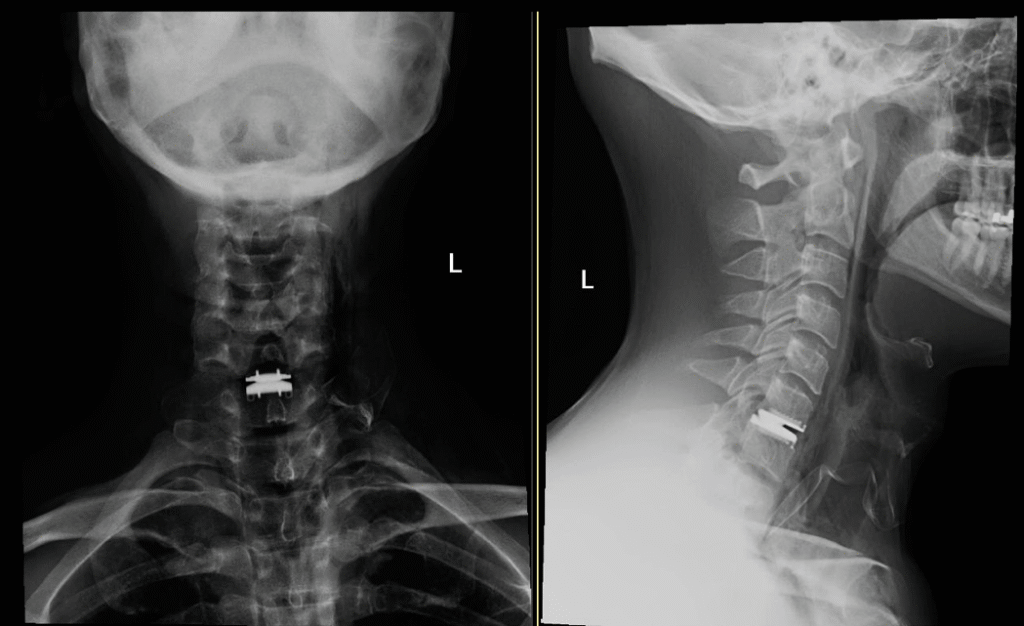

Hybrid Surgery

hybrid